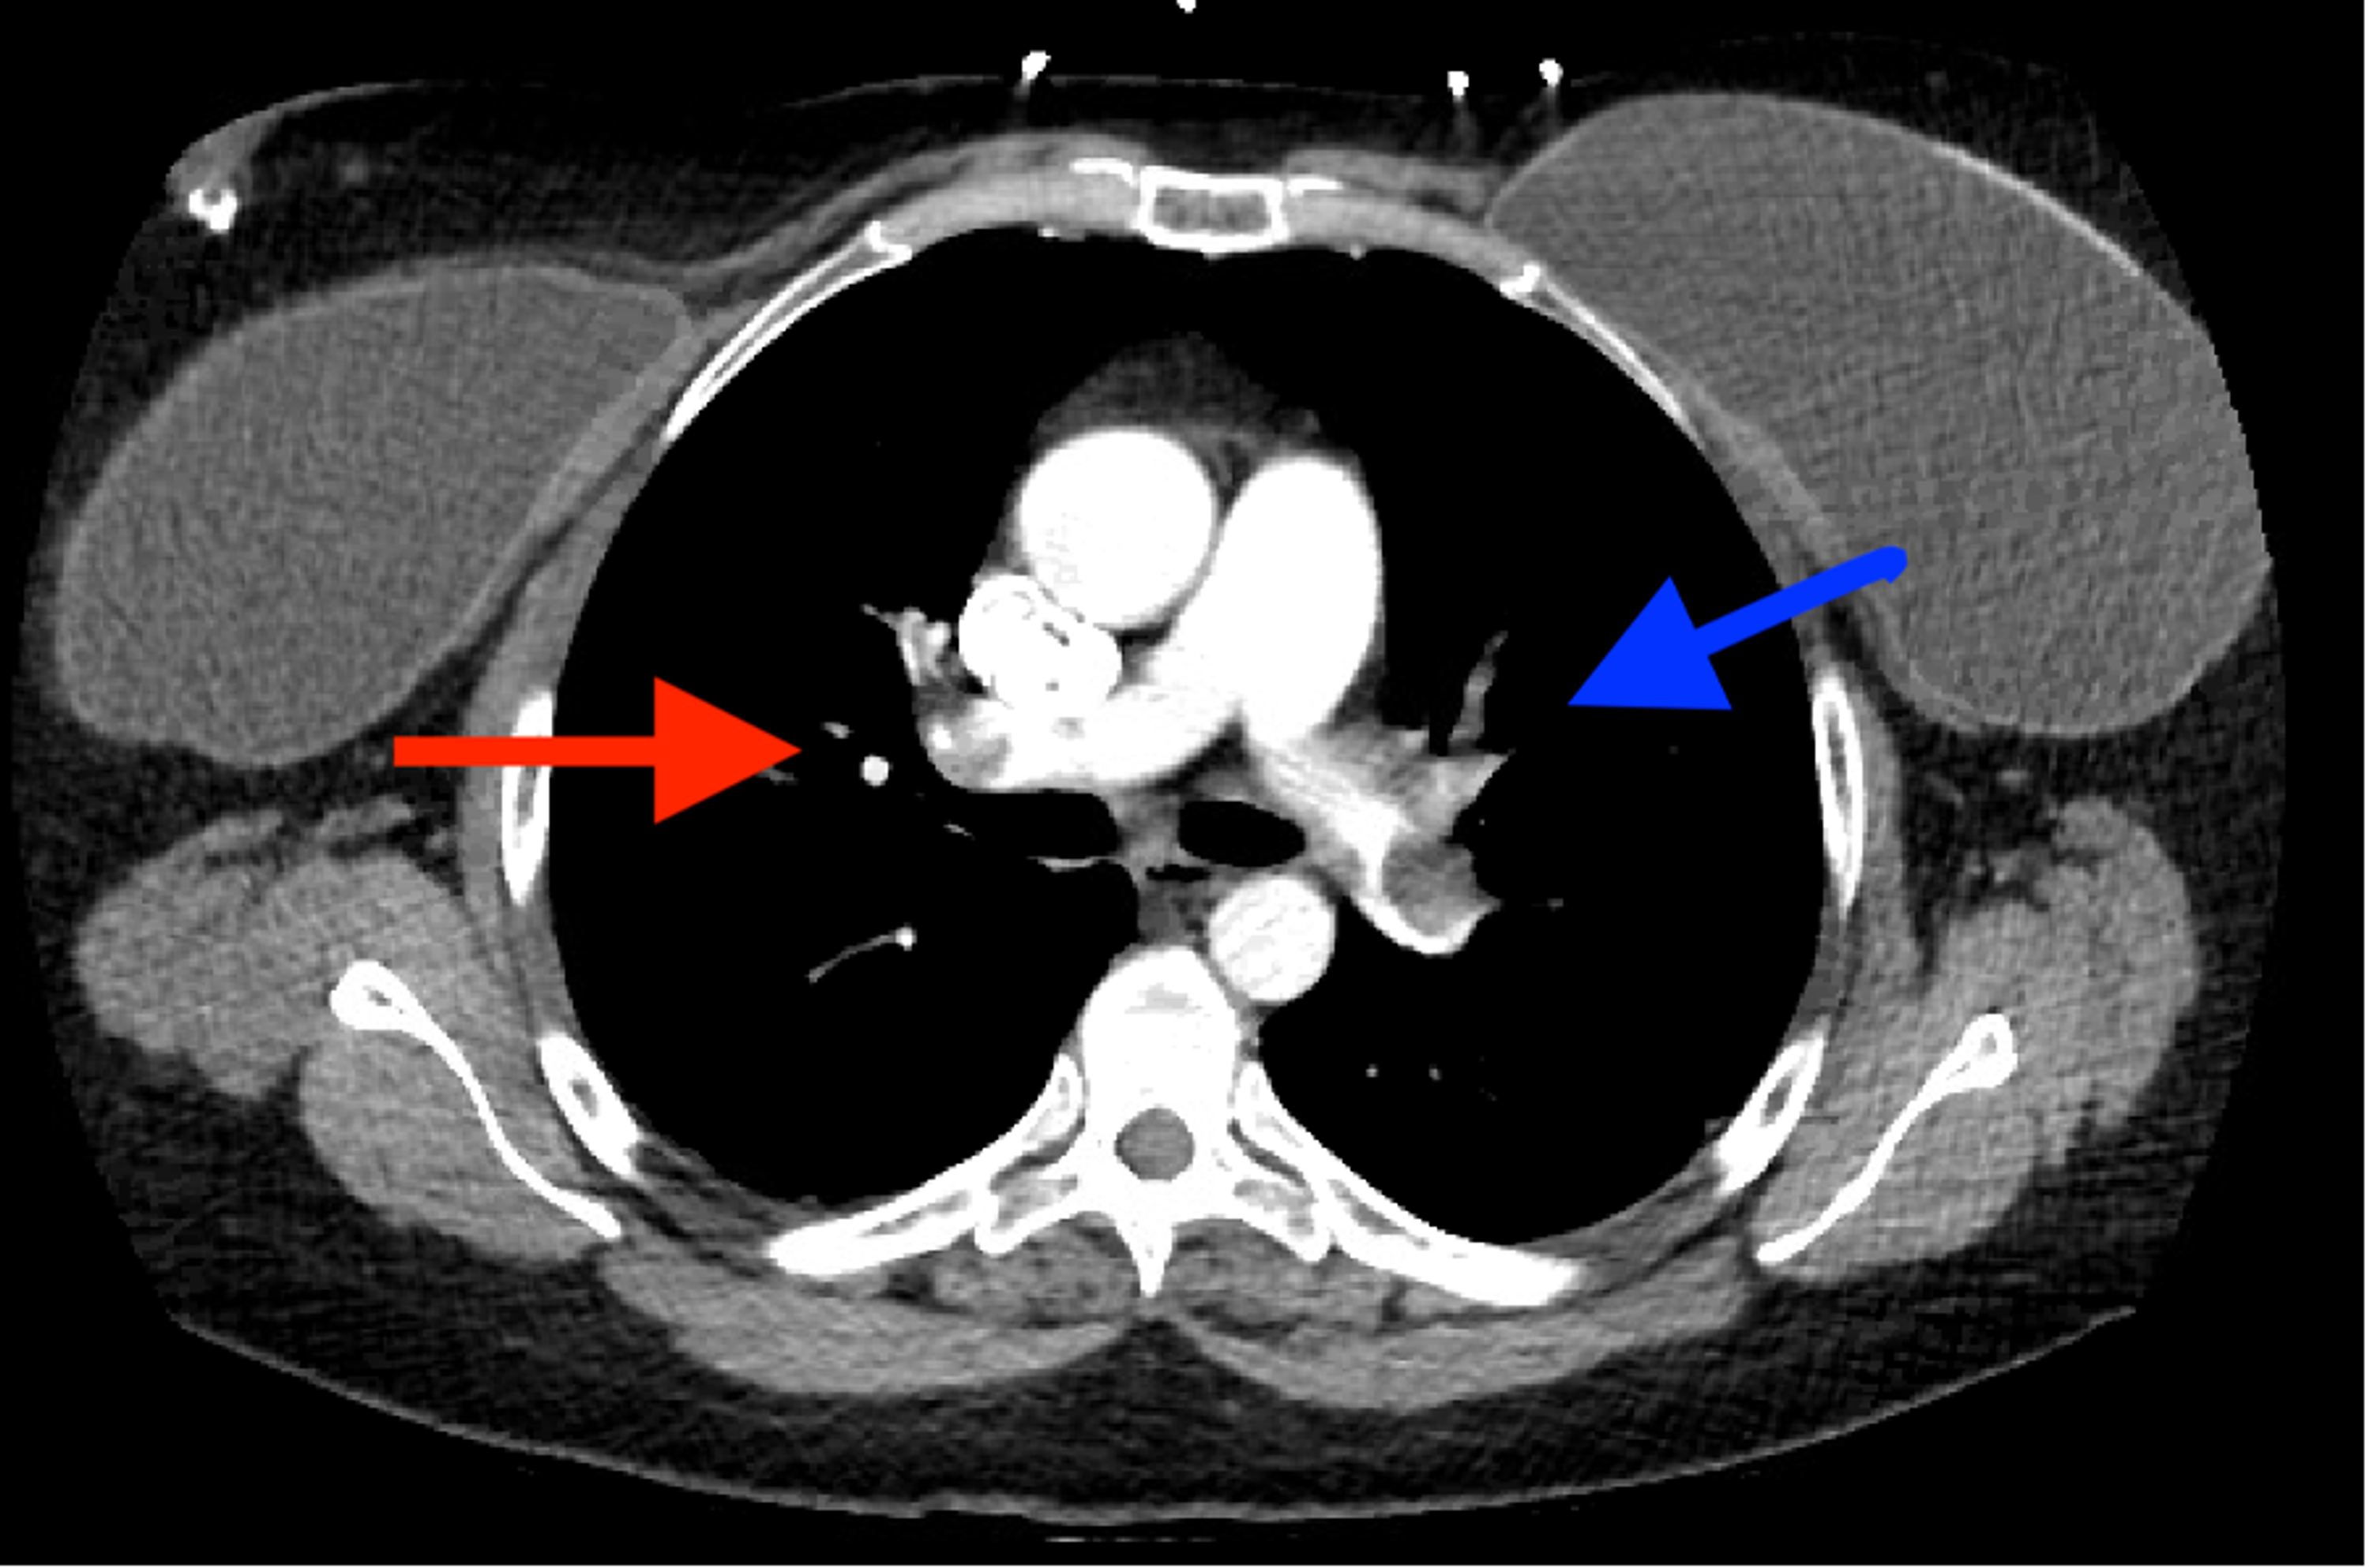

Pulmonary Thromboembolism Undergraduate Diagnostic Imaging Fundamentals

From openpress.usask.ca

Pulmonary Thromboembolism Undergraduate Diagnostic Imaging Fundamentals What Does Pulmonary Embolism Look Like On X Ray Pulmonary embolism (pe) refers to partial or complete embolic occlusion of one or more pulmonary arteries, most commonly due to thrombus. Pe is apparent as a ventilated. The radiologist directs the tip of the catheter into the different branches of the right and left pulmonary arteries and injects the contrast dye,. Known as a computed tomographic pulmonary angiography (ctpa), this. What Does Pulmonary Embolism Look Like On X Ray.